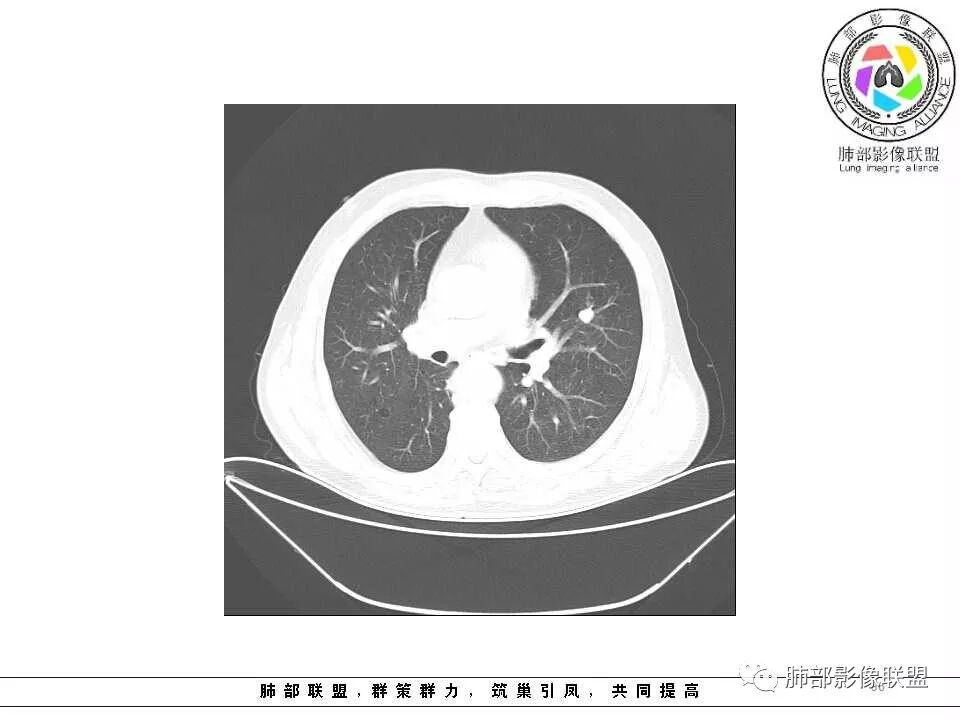

影像学特点:肺气肿背景下在大概一年的时间里出现了一个光滑的小结节,因为图像给的不是太薄,与支气管的关系判断不清,从结节周围出现斑片状炎症来判断,应该考虑结节位于支气管内,周围是阻塞性炎症,这样比较容易解释咯血

老年男性,左肺舌段见多个小结节灶及斑片状高密度灶、磨玻璃影,结节灶边界清晰,光滑,无明显分叶,密度均匀,周围病灶密度不均,一年内生长,考虑恶性肿瘤并阻塞性肺炎出血,小细胞可能大。

老年男性,肺气肿基础。约一年时间出现左肺上叶舌段支气管近端结节影,远端斑片样阴影,边缘模糊。考虑近端恶性占位,远端有阻塞性炎症。

老年男性,两肺可见小叶中央型肺气肿,提示应该有抽烟史。2016年片,右肺门支气管稍模糊,考虑慢性感染,纵膈淋巴结稍大。但2017年左肺上叶新发占位,堵塞支气管,引起局部肺不张伴感染,且纵膈淋巴结较2016年变大,患者同时伴有咯血,考虑恶性。鳞癌?类癌?小细胞?

肺气肿背景,2016年左肺上叶上舌段见微结节,2017年5月左肺结节增大,密度均匀,边缘光滑锐利,与邻近血管关系密切,血管贴壁走行,外侧见尖状突起,下舌段片状影,沿着支气管走行,内有粘液栓,考虑鳞癌,鉴别小细胞肺癌。

肺气肿背景,2016年左肺上叶上舌段见微结节,一年后左肺结节增大,密度均匀,边缘光滑、膨隆,似见小分叶,下舌段片状影,沿着支气管走行,内,老年患者,咯血1月。考虑恶性病变并阻塞性肺炎,鳞癌?注意鉴别结核。